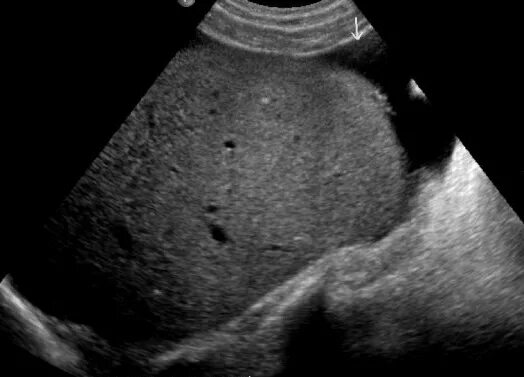

Асцит в малом тазу